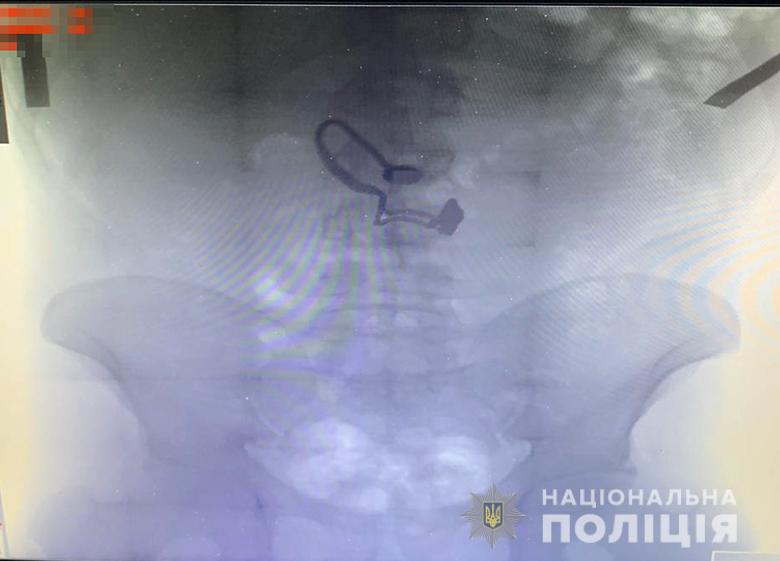

Во время поверхностного осмотра у мужчины нашли кошелек потерпевшей. Потом он признался полицейским, что сорванную цепочку проглотил. Во время медосмотра на рентген снимке задержанного врачи обнаружили украшение.